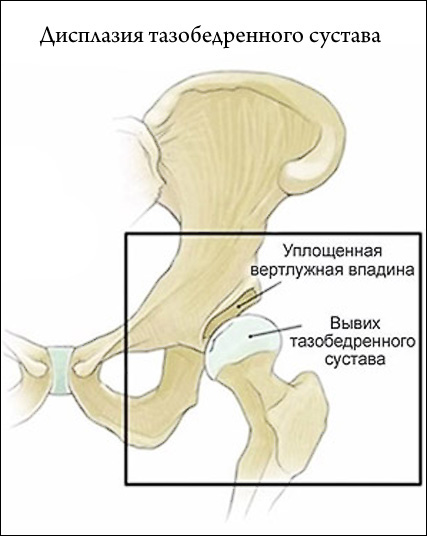

Суглоби при вагітності

Огляд дисплазії тазостегнових суглобів у новонароджених: причини, діагностика, лікування